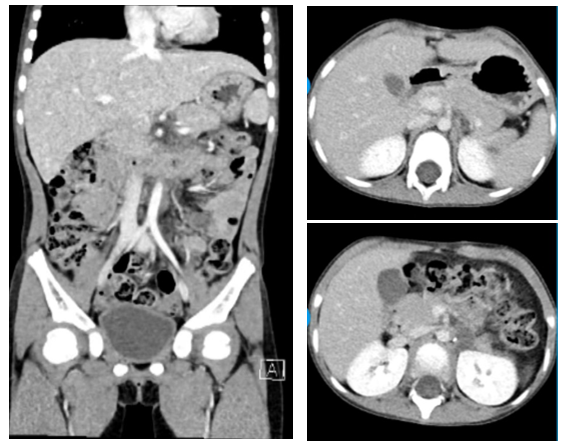

2024-4-11

复查腹盆CT示:左腹膜后团片状稍低密度灶,考虑术后改变(图6)。腹主动脉旁小淋巴结,盆腔未见明显异常。胸骨和髂骨骨髓涂片均未见肿瘤。

图6:术后CT